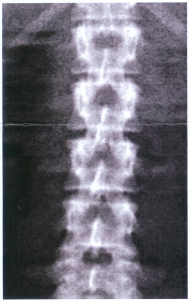

Kwestie van een ruggengraat hebben…

Lees meer: Kwestie van een ruggengraat hebben……want anders had deze pica nooit genomen kunnen worden. Mijn ruggenwerveltjes ge-x-rayt: Die lijn in het midden is de vouw van het printje. Geen medisch manco…